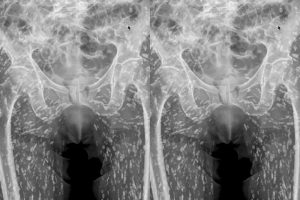

Ακτινογραφία αποκάλυψε ότι ένας άνδρας έχει μέσα του εκατοντάδες αυγά κεστώδη σκώληκα.

Ο αμερικάνος γιατρός Sam Ghali μοιράστηκε την ακτινογραφία του ασθενούς του στο X (πρώην Twitter) σχολιάζοντας πως είναι ««μία από τις πιο τρελές ακτινογραφίες που έχω δει ποτέ».

«Πρόκειται για μια πάθηση γνωστή ως κυστικέρκωση», πρόσθεσε ο ίδιος.

«Σε αυτόν τον ασθενή έχουν μεταφερθεί σε μεγάλο βαθμό στους μυϊκούς και μαλακούς ιστούς των ισχίων και των ποδιών», συμπλήρωσε ο ίδιος.

Η ανάρτηση του γιατρού: